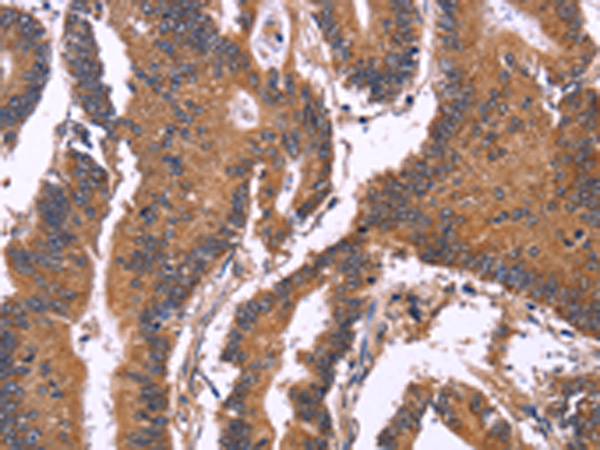

The image is immunohistochemistry of paraffin-embedded Human colon cancer tissue using 47243(SEPT7 Antibody) at dilution 1/50.(Original magnification: 200)

The image is immunohistochemistry of paraffin-embedded Human gastric cancer tissue using 47243(SEPT7 Antibody) at dilution 1/50.(Original magnification: 200)